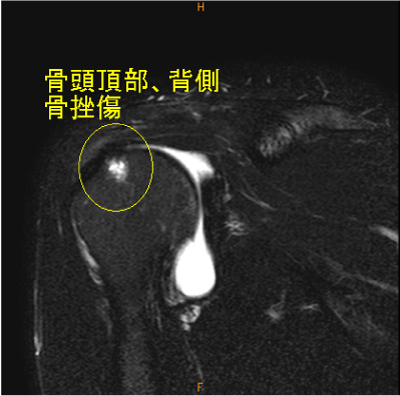

MRI所見

外傷は何があるか判らない。

長頭腱の不完全断裂